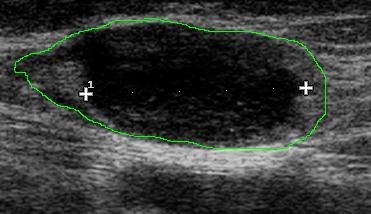

Az alsó képen körülrajzolt terület a teljes nyirokcsomó kontúrját jelöli; jól látszik az asszimetrikusan kiszélesedett, echoszegény köpenyzóna

UH, FTAB: Bal oldalon inguinalisan a tapintható terimének megfelelően egy kb.

4 cm-es nyirokcsomó látható, melynek köpenyzónája 23 mm-es szakaszon kiszélesedett. E területen a köpenyzóna ovoid, csaknem echomentes, seprűszerűen hypervascularisalt. E területről UH vez. FTAB-t